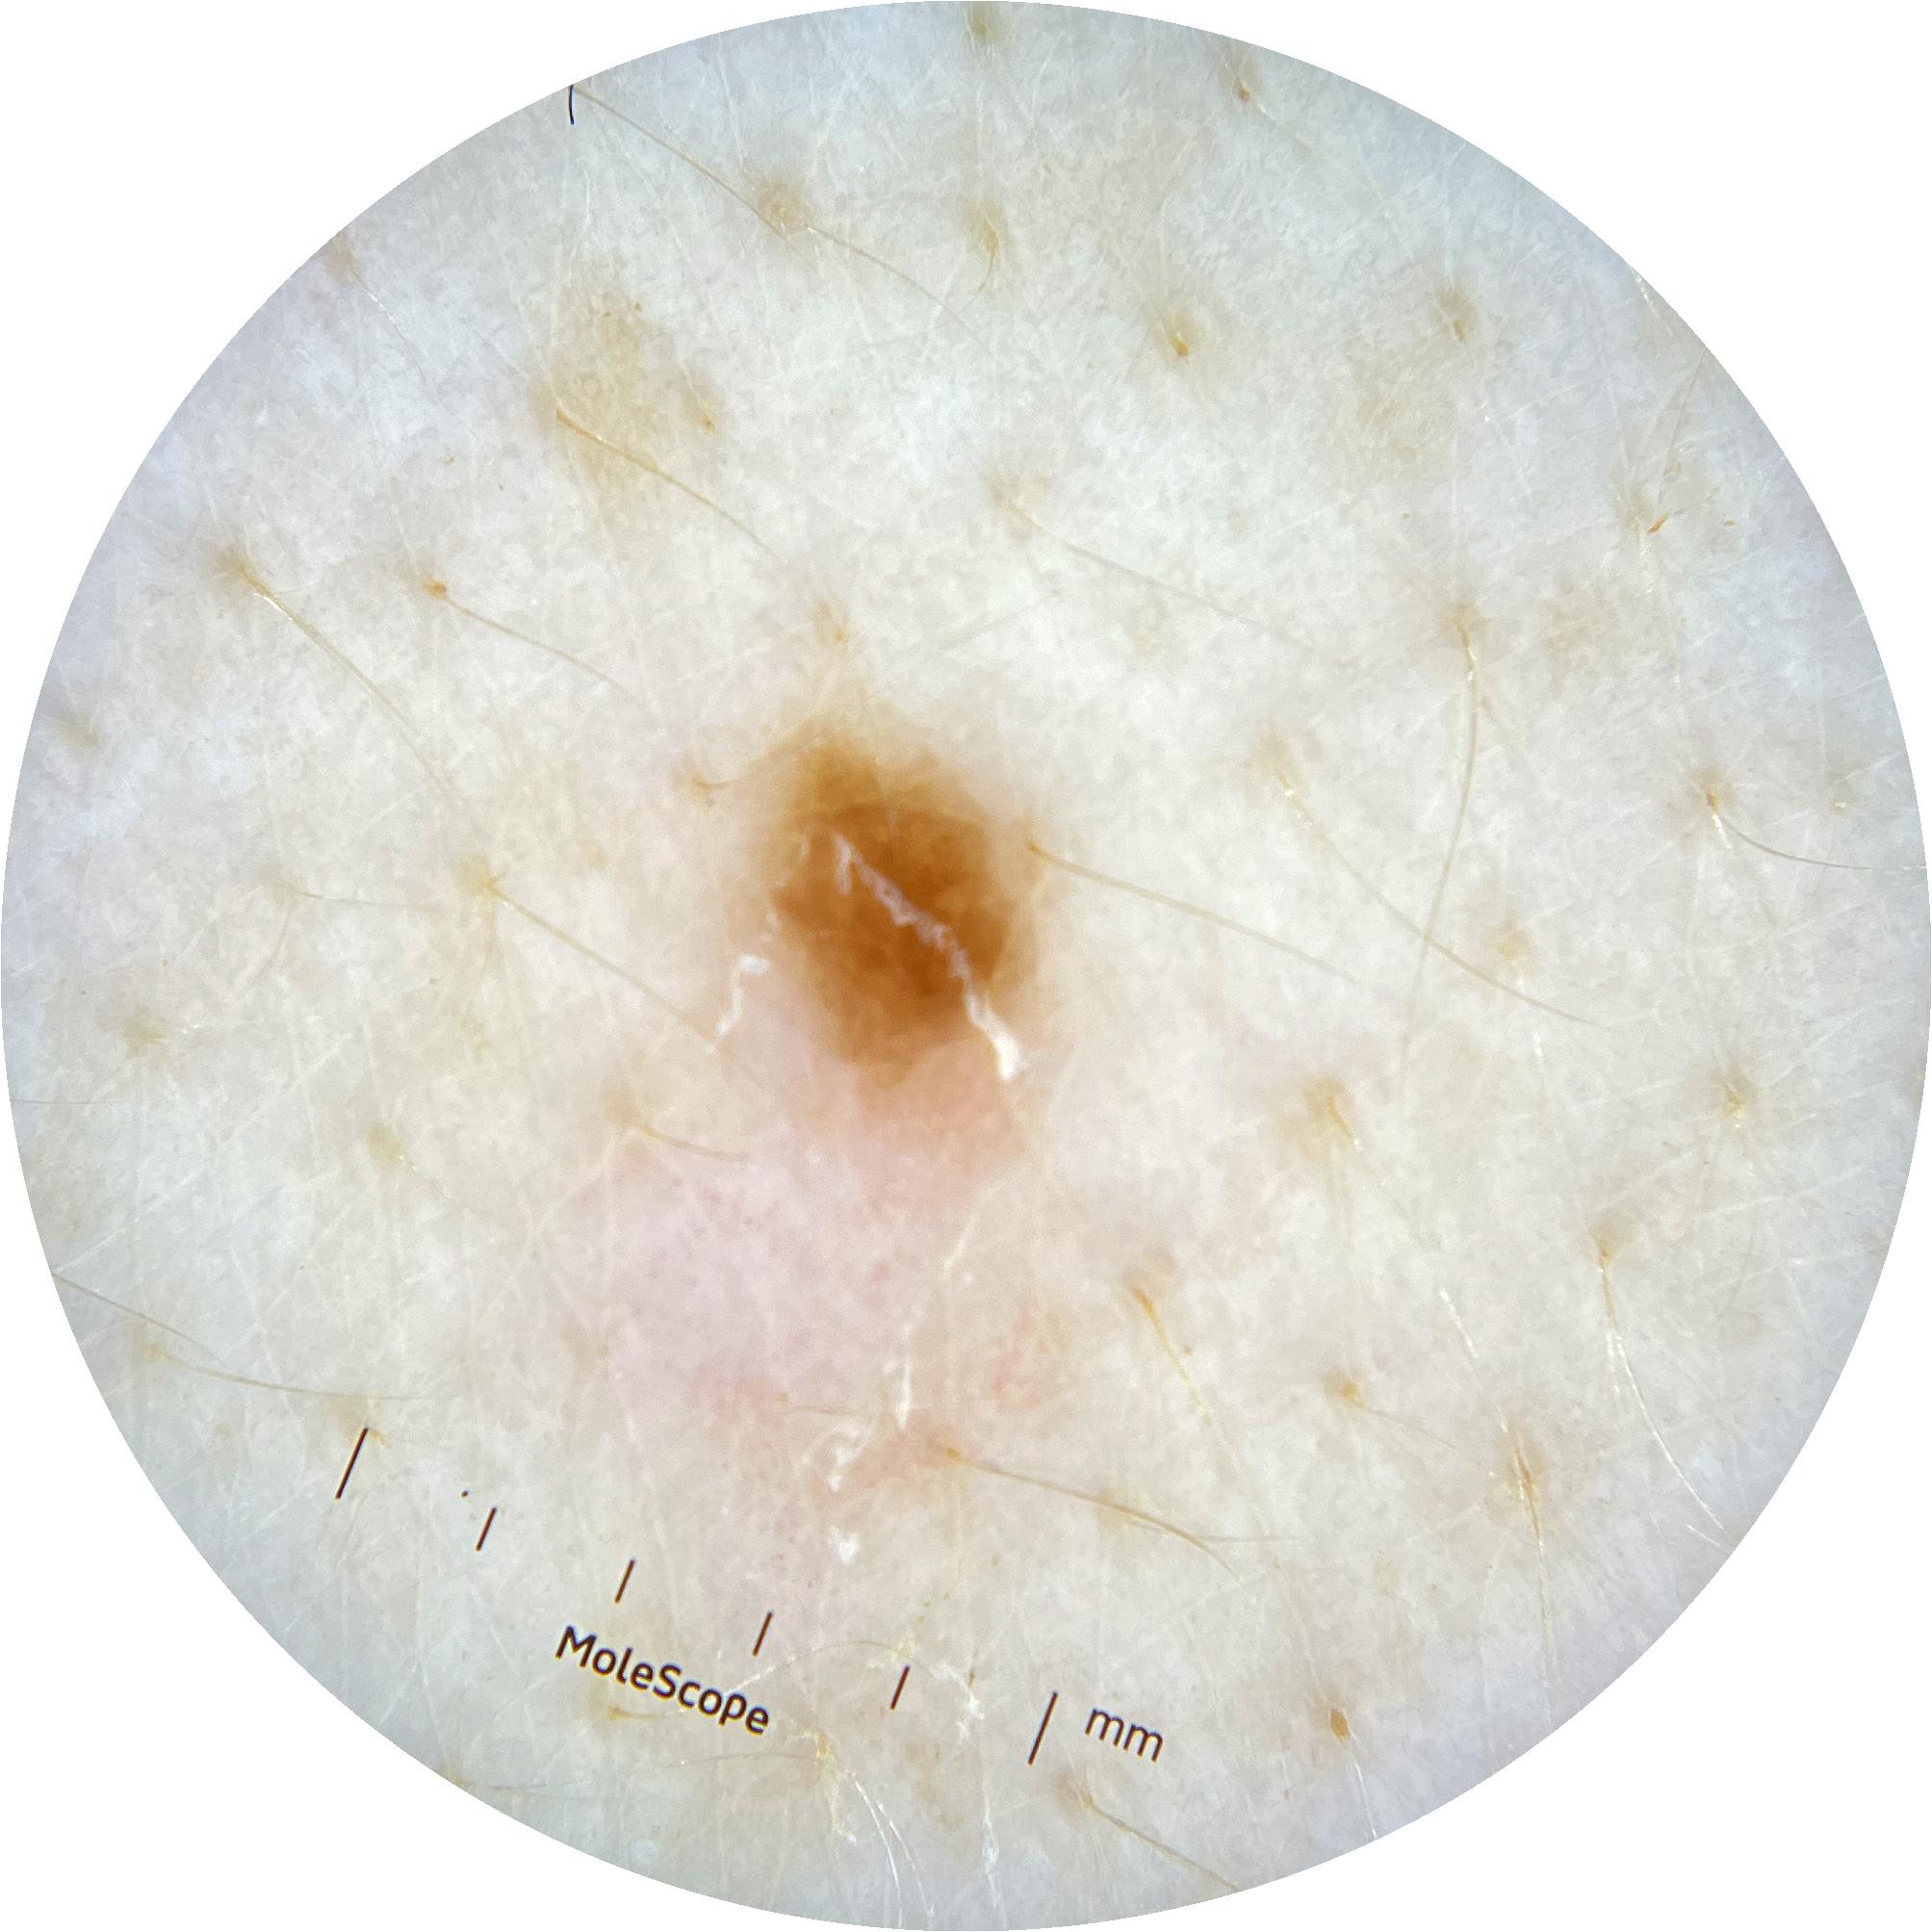

ISIC_0301375

1986 x 1986

acquisition_day 331

age_approx 35

anatom_site_1 Trunk

anatom_site_2 Anterior trunk

anatom_site_general anterior torso

diagnosis_1 Benign

diagnosis_confirm_type single image expert consensus

image_type dermoscopic

personal_hx_mm True

sex female